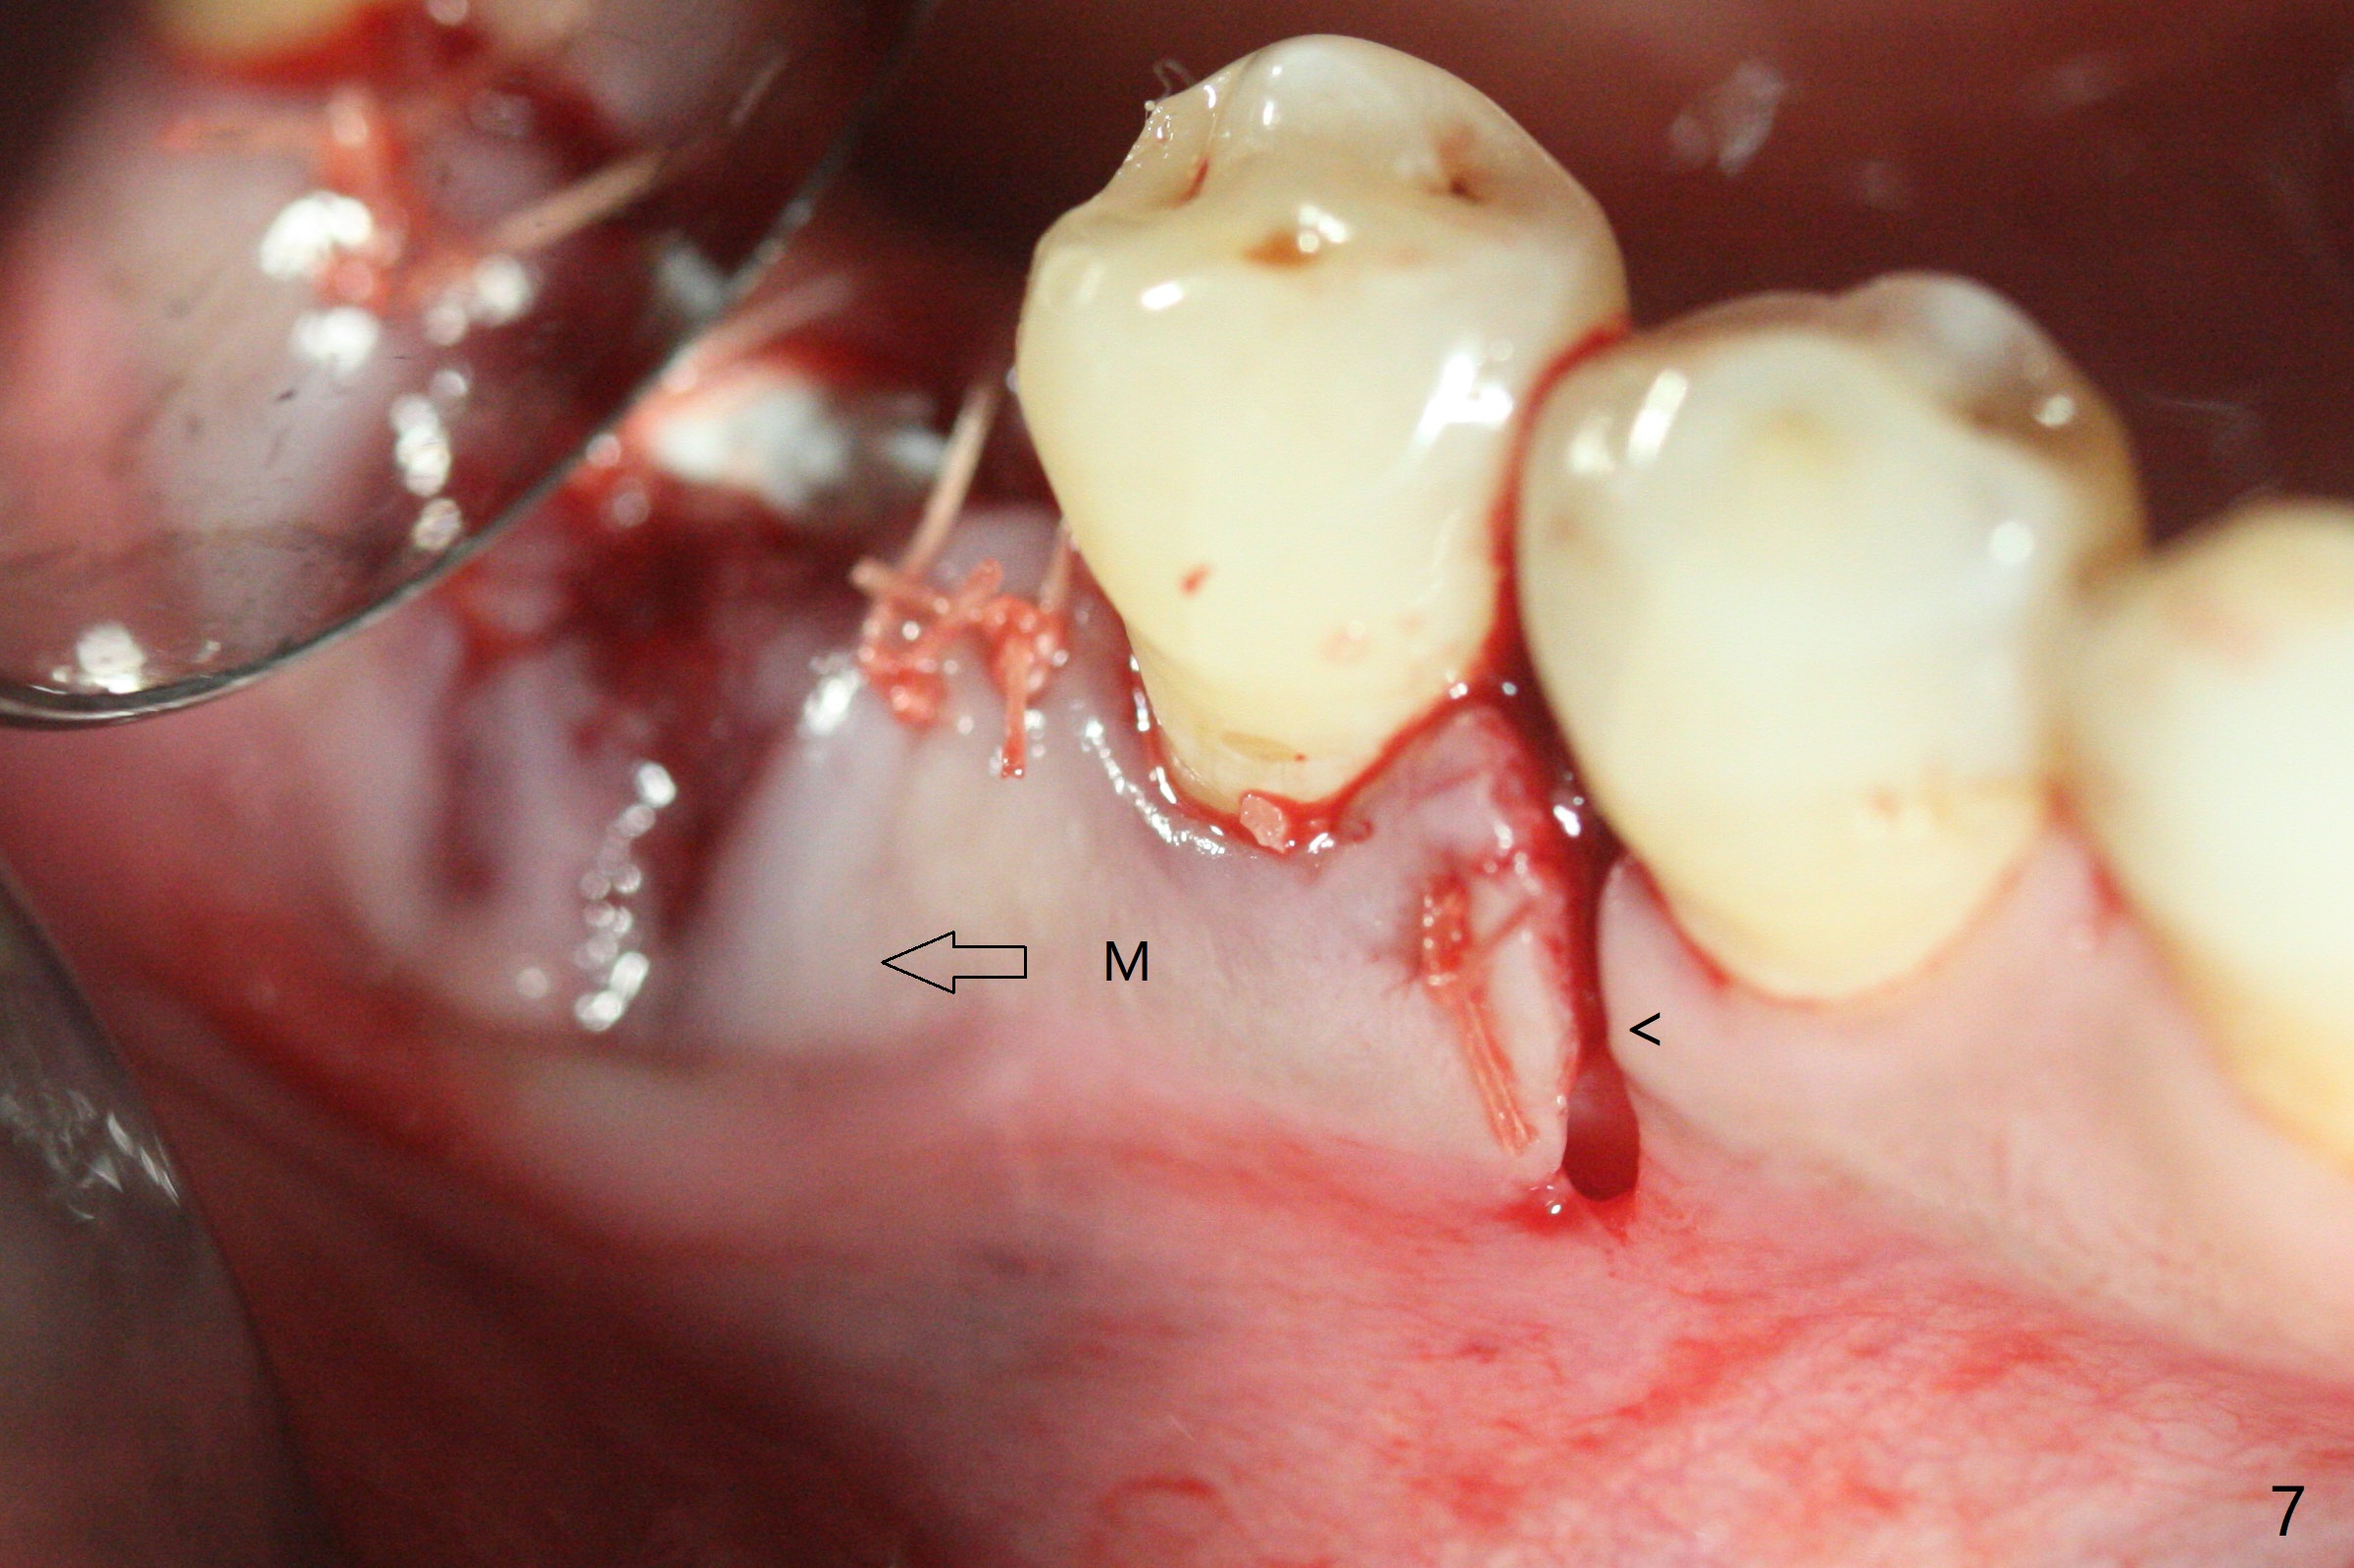

In spite of use of water pik, the coronal threads of the implant at #30 remain exposed 2 months postop (Fig.1). Envelop incision with mesial and distal accessory release ones reveals buccal bony defect (Fig.2). After 2nd spin (1500 RPM for 10 minutes), PRF forms in the red tube (Fig.3 yellow gel-like). Following use of Titanium brush, sticky bone is place (not so bone block-like, Fig.4), followed by a large piece of PRF membrane (from the red tube of Fig.3), Cytoplast (Fig.5,6 white porous) and a small piece of PRF membrane (from the white tube, next to the thin gingiva). The distal (Fig.6 D) and mesial (Fig.7 M) flaps are approximated (arrows without suture) as much as possible as well as lingual. 4-0 Polyglycolic Acid suture is used. Periodontal dressing dislodges 5 days postop. When the patient returns 1 week postop, he is pain free. Although Cytoplast is exposed, the surrounding gingiva seems to be healthy (Fig.8). Later the permanent crown of #31 is temporarily cemented with OHI. It appears that Cytoplast could be used to cover PRF membranes for soft tissue defect, followed by immediate provisional at the stage of immediate implant. The discolored (apparently contaminated) Cytoplast seems to be expelled 6 weeks postop (Fig.9). When the latter is removed, the soft tissue looks normal (Fig.10). Two weeks later, the apparently normal, but thin gingiva forms over the former granulation tissue (Fig.11 *, as compared to Fig.10). There is not enough bone coronal to the implant plateau 2 months post graft (Fig.12). Three months later, bone graft will be re-placed possibly with uncover.